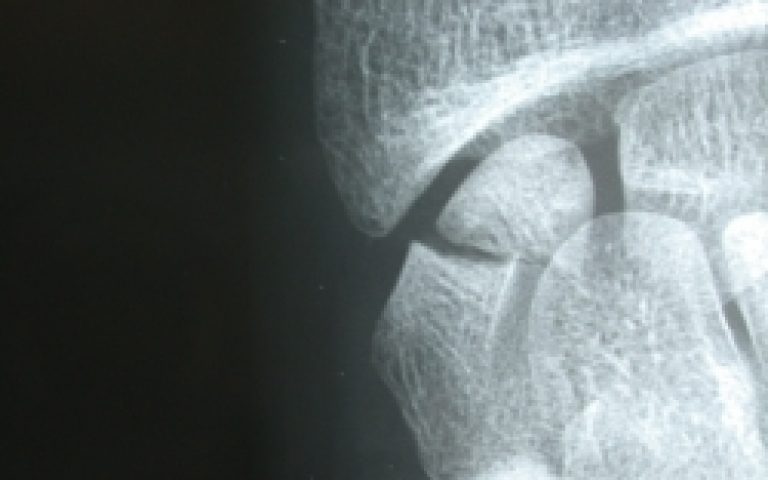

Pathologies de la Main et du poignet Pseudarthroses du scaphoïde

Pseudarthroses du scaphoïde